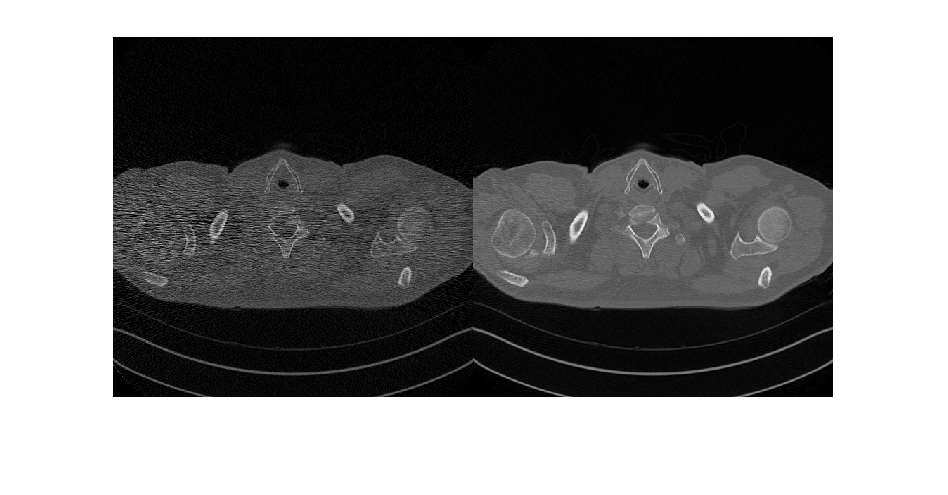

Глубокое обучение использует нейронные сети, чтобы изучить полезные представления функций непосредственно из данных. Например, можно использовать предварительно обученную нейронную сеть, чтобы идентифицировать и удалить артефакты как шум от изображений.

Обучите и примените нейронные сети шумоподавления

Используйте предварительно обученную нейронную сеть, чтобы удалить Гауссов шум из полутонового изображения или обучить вашу собственную сеть с помощью предопределенных слоев.